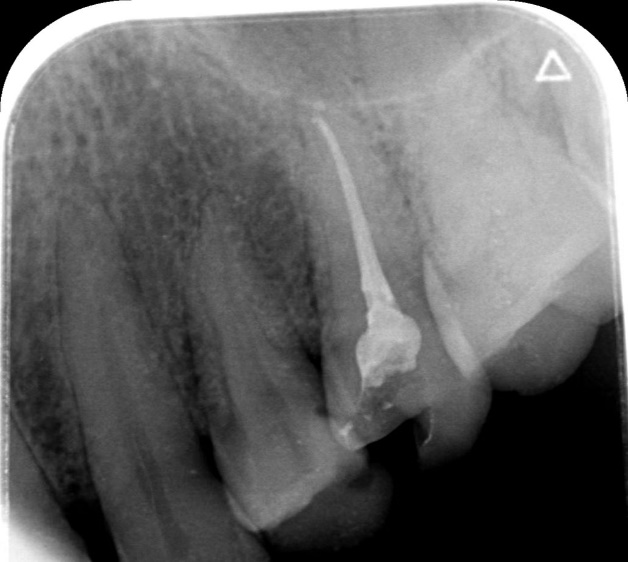

根尖片(小牙片)

根尖片用于检查单个牙齿的牙体、牙周及根尖周病变。根尖片投照技术有两种:分角线技术及平行技术。根管治疗过程中通常拍摄小牙片看牙胶尖放置是否到位,根管治疗后拍摄小牙片可观察牙胶尖是否充填到位。

根管充填完成后观察根管充填是否到位